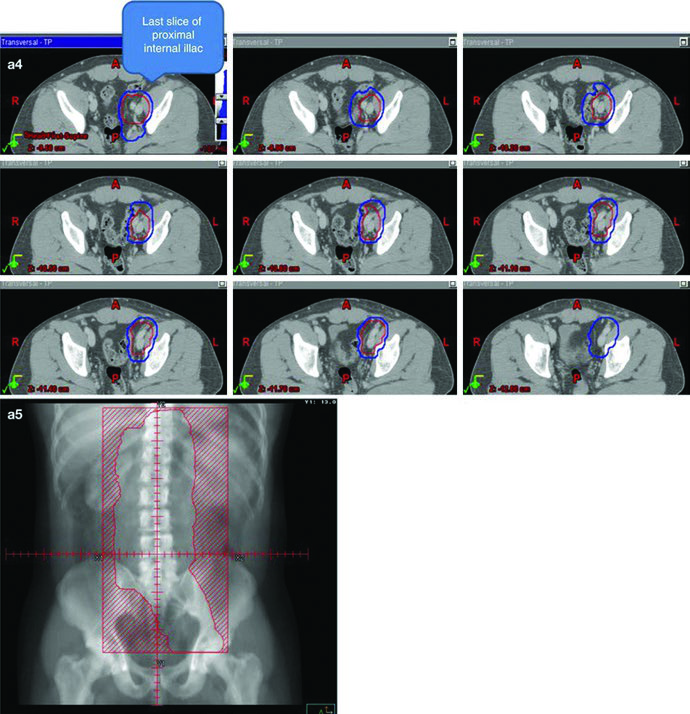

O ponto técnico mais útil é que o dogleg não nasce do zero. Ele começa com o mesmo contorno de cava inferior e aorta usado no estágio I e, em seguida, incorpora vasos ilíacos comuns, porções proximais dos ilíacos internos até a emergência da glútea superior e vasos ilíacos externos até a borda superior do acetábulo, com expansão de 1,2 cm respeitando limites anatômicos. Depois disso, o capítulo pede contorno da doença nodal grosseira, o GTV, com expansão de 0,8 cm respeitando a anatomia, formando um CTV nodal. A união do CTV vascular com o CTV nodal produz o CTV inicial.

Esse campo inicial recebe expansão de 0,5 cm mais 0,7 cm até a borda do bloco para compor o PTV inicial, ainda na faixa de 20 a 25,5 Gy com frações de 1,5 a 2,0 Gy. O boost em conedown segue a mesma lógica geométrica aplicada ao CTV nodal, também com 0,5 cm mais 0,7 cm até a borda do bloco, até completar 30 a 36 Gy em 2 Gy por fração. O capítulo ainda acrescenta uma regra simples e prática para a doença visível: garantir margem de 2 cm ao redor de toda adenopatia grosseira visível.

Os marcos anatômicos ajudam a não perder o eixo do campo. Superiormente, o limite permanece no topo de T11, com a mesma nota de que algumas fontes usam topo de T12. Inferiormente, o capítulo posiciona o limite no topo do acetábulo, embora algumas fontes recomendem o meio ou a base do forame obturatório. A borda lateral acompanha as pontas dos processos transversos das vértebras lombares, tipicamente em torno de L3, considerando a posição dos rins, e se estende inferiormente para cobrir a borda lateral do acetábulo. Para seminoma à esquerda, a cobertura do hilo renal esquerdo volta a aparecer como opcional.

A figura de boost fecha esse raciocínio muito bem. Ela mostra, em um exemplo de estágio IIA, a diferença entre GTV em amarelo, CTV em vermelho e PTV em azul. Não é só uma ilustração bonita; é a prova visual de que o capítulo separa volume eletivo, volume inicial e volume de reforço com precisão suficiente para orientar planejamento real.

| CTV inicial | Usar os mesmos contornos e expansões de cava inferior e aorta descritos na Table 27.1. Depois, contornar vasos ilíacos comuns, porções proximais dos ilíacos internos até a origem da glútea superior e vasos ilíacos externos até a borda superior do acetábulo, com expansão de 1,2 cm respeitando limites anatômicos. Contornar a doença nodal grosseira (GTV) e expandir 0,8 cm respeitando limites anatômicos. Combinar CTV vascular e CTV nodal para formar o CTV inicial. |

Borda superior: topo de T11 (algumas fontes recomendam topo de T12) [6]. Borda inferior: topo do acetábulo (algumas fontes recomendam meio ou base do forame obturatório) [6]. Borda lateral: pontas dos processos transversos lombares, tipicamente em L3 com consideração da localização renal, estendendo-se para cobrir a borda lateral do acetábulo na porção inferior do campo. |

| PTV inicial 20–25,5 Gy em 1,5–2,0 Gy por fração |

Expandir o CTV inicial em 0,5 cm + 0,7 cm até a borda do bloco. | Para seminoma à esquerda, os estudos de mapeamento nodal sugerem que cobrir o hilo renal esquerdo é opcional [7]. |

| PTV de boost em conedown Total de 30–36 Gy em 2 Gy por fração |

Expandir o CTV nodal em 0,5 cm + 0,7 cm até a borda do bloco. | Garantir margem de 2 cm ao redor de toda adenopatia grosseira visível. |